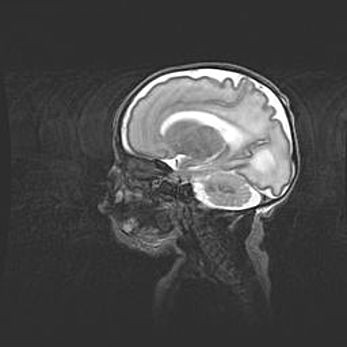

Наружная гидроцефалия с возможной атрофией височных областей.

Возраст: 28 дней

Вес: 3670 г

Пол: мужской

Окружность головы: 38 см

Срок гестации: 40 недель

Гидроцефалия головного мозга у новорожденных – это заболевание, которое характеризуется скоплением избыточного количества спинномозговой жидкости в желудочковой системе головного мозга в результате затруднения её перемещения от места выработки к месту поглощения в кровеносную систему или вследствие нарушения абсорбции. При открытой наружной форме гидроцефалии у новорожденных расширяются и переполняются субарахноидные пространства.

При нормотензивных  формах,  которые,  как  правило,  являются  следствием  перенесенных ишемических  повреждений  паренхимы  мозга,  возможно  сочетание микроцефалии  с нормотензивной гидроцефалией. В основе данных изменений лежит атрофия больших полушарий с преимущественной  локализацией  в  лобно-височных  областях.